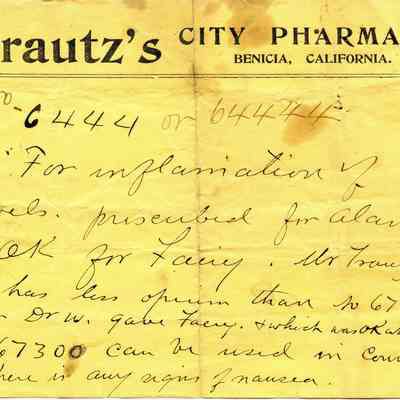

Bill Bill

Bill Bill

Bill Bill

Bill Bill

Bill Bill

Bill Bill

Bill Bill

Bill Bill

Bill Bill

Bill Bill

Bill Bill

Bill Bill

Bill Bill

Bill Bill

Bill Bill

Bill Bill

Bill Bill

Bill Bill

Bill Bill

Bill Bill

Bill Bill

Bill Bill

Bill Bill